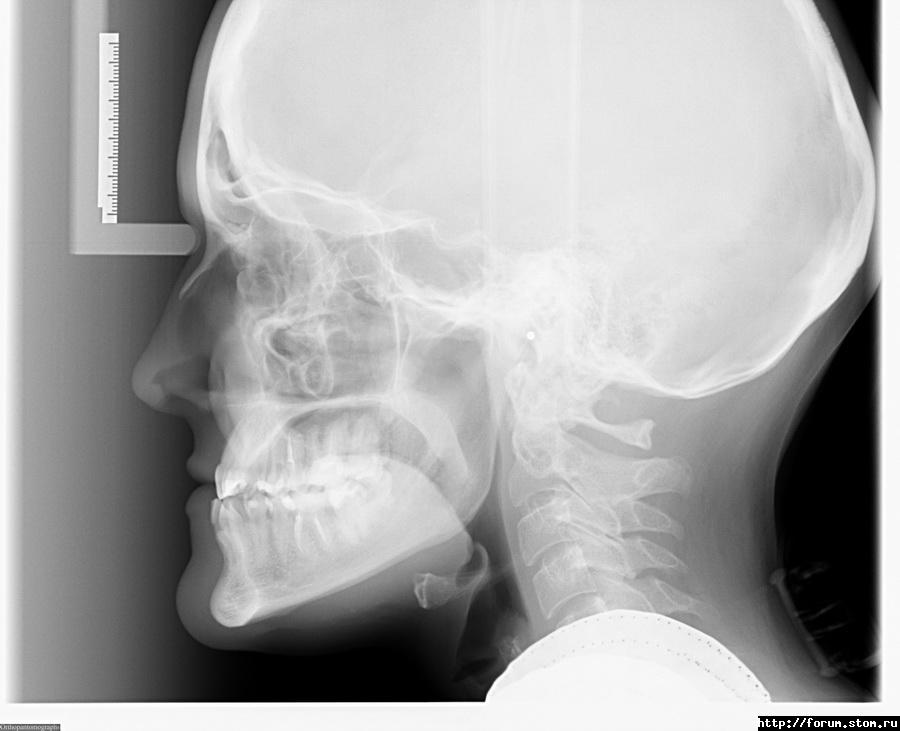

Премоляр Опубликовано 6 ноября, 2011 Поделиться Опубликовано 6 ноября, 2011 Хотелось бы взглянуть на лицо и ТРГ....как минимум Ссылка на комментарий

Inn-ka Опубликовано 6 ноября, 2011 Автор Поделиться Опубликовано 6 ноября, 2011 (изменено) Извиняюсь, раз пять правила-уменьшала снимки. Слишком много пыталась разместить. ТРГ - как выглядит? Это не тот снимок, что у меня размещен?Еще бы знать, как лицо снимать, дома самостоятельно та еще задача :-( Изменено 6 ноября, 2011 пользователем Inn-ka Ссылка на комментарий

Премоляр Опубликовано 6 ноября, 2011 Поделиться Опубликовано 6 ноября, 2011 Да...теперь есть ТРГ Ссылка на комментарий